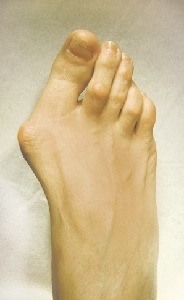

Efectul clinic al tratamentului flatfoot (oprire apariție înainte și după intervenția chirurgicală)

Efectul clinic al tratamentului flatfoot (stiva aspect inainte si dupa operatie)

Pacientul a avut o oportunitate de a ajunge pe degetele de la picioare si sa poarte pantofi cu tocuri